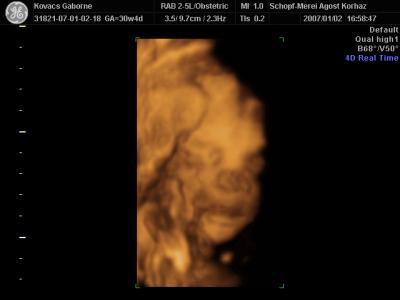

Az elsők a 19. héten, a második sorozat pedig a 30. héten készült.

Az elsők a 19. héten, a második sorozat pedig a 30. héten készült.

2007.01.20 22:33